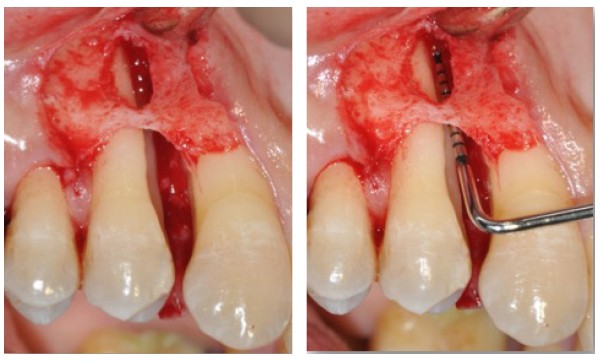

Quand et comment intervenir par voie chirurgicale ? C’est la question à laquelle Filippo Graziani tentera de répondre car, si les techniques de débridement non chirurgical ont permis de repousser les limites des indications chirurgicales, celles-ci sont encore nécessaires (fig. 3a et b). Le choix chirurgical dépend à la fois des objectifs définis initialement avec le patient et des résultats du traitement étiologique. Les séances de chirurgie peuvent être généralisées ou localisées, et faire appel aux différentes techniques d’assainissement, de résection ou d’addition, avec la possibilité de régénération tissulaire par apport de biomatériaux.